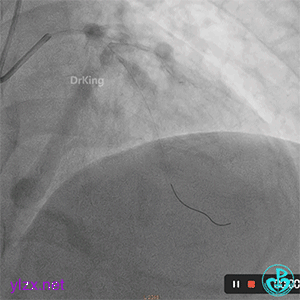

08 1个月后复查

RCA粗大全程瘤样扩张明显,自近段闭塞,TIMI血流0级;可见自身桥侧支逆供RCA远段。

LM未见明显狭窄,LAD开口至近段明显瘤样扩张,自近段闭塞,TIMI血流0级,D1瘤样扩张,TIMI血流2级;可见D1逆供LAD中远段及RCA中远段。

LCX发育小,内膜不光滑,TIMI血流3-级,逆供RCA中远段。